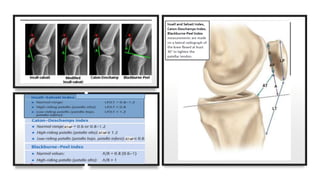

Measurements around knee